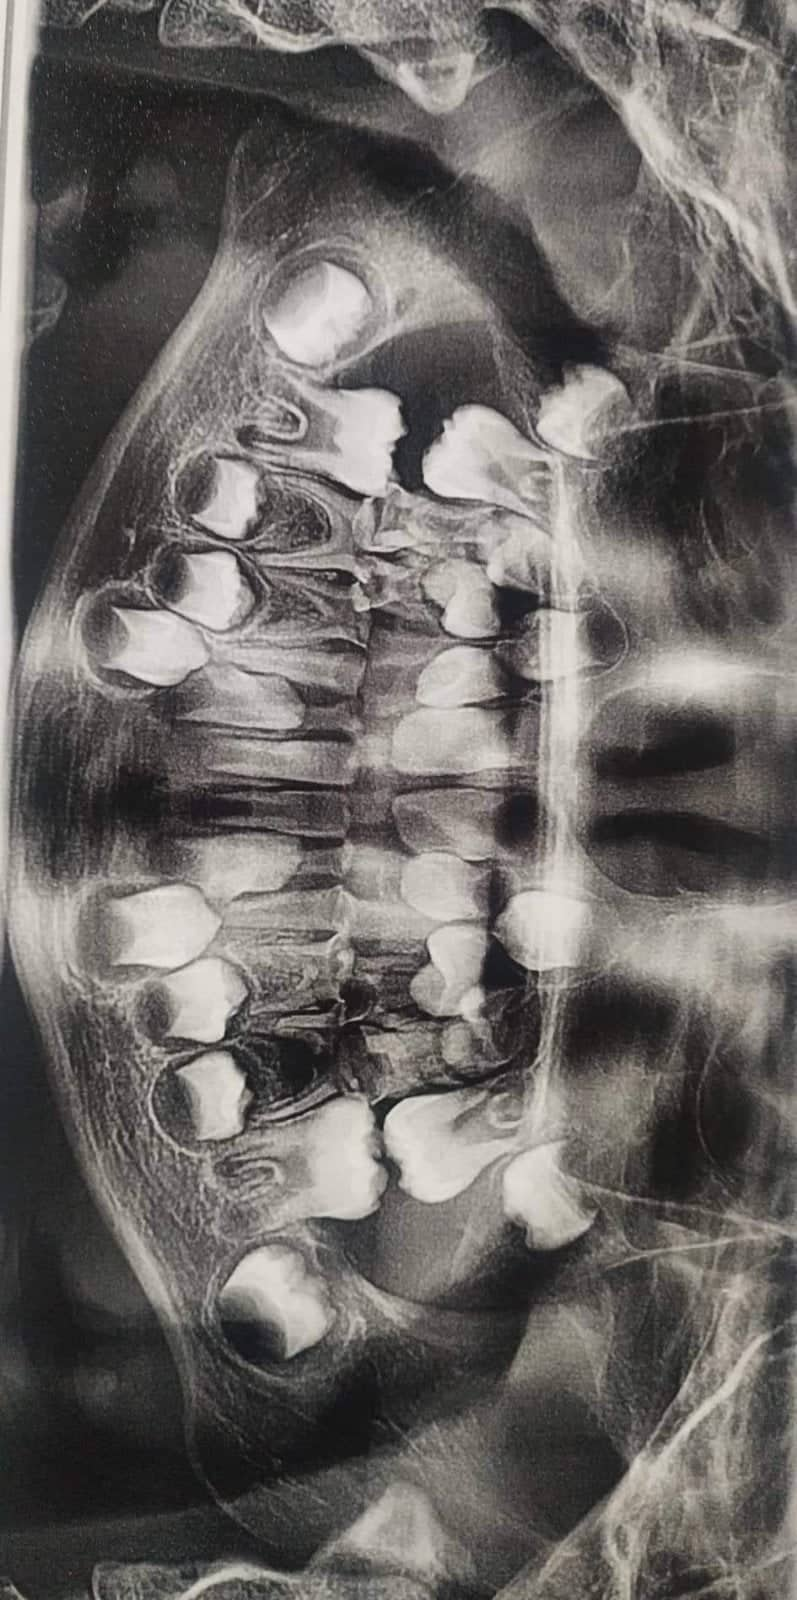

Edit Record Check our patient data records. Add patient information Patient Info Profile picture Last Name First Name Middle Name Birthdate Age Street Barangay City Country Zip Code Contact number Email Procedure 9/16/22- Check up. For exo primary teeth 10/12/22- Pulpo 74,84,83 - Exo 51 to 55 - 61 to 65 - 73,75,72 - 82, 84 , 85 PX. - under IVCS Rx: cephalexin 250mg/5ml 2x a day- 6ml Ibuprofen + paracetamol 100mg/5ml= 10ml prm 10/19/22 - SEALANT #36, #46 File 310405601_475726681173881_7030259484465437471_n.jpg File 2 299940667_817781262749970_6587528825403293388_n.jpg File 3 File 4 File 5 File 6 File 7 File 8 File 9 File 10 File 11 File 12 File 13 File 14 File 15 File 16 File 17 File 18 File 19 File 20 Retain Record Retain Record Yes No Save Your Changes